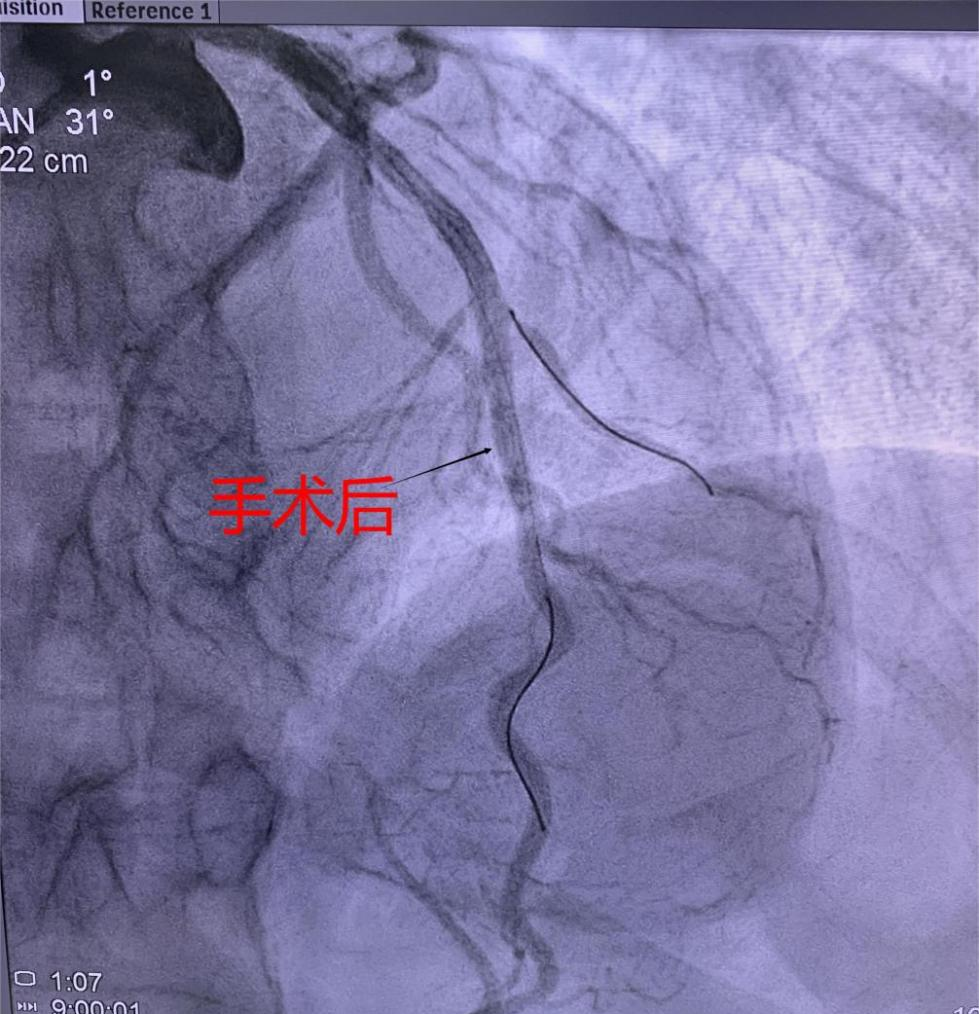

支架植入術(shù)前經(jīng)過充分預(yù)擴張,按照規(guī)范的可吸收支架操作流程,快速送入可吸收支架到靶血管病變部位,精準(zhǔn)定位后14個大氣壓釋放,生物可吸收支架后擴球囊選擇不超過支架直徑0.25mm的非順應(yīng)球囊擴張。充分球囊后擴張,以保證支架貼壁良好,血流速度加快,造影完美,手術(shù)順利結(jié)束。

(可吸收支架植入手術(shù)中)及(手術(shù)造影圖)